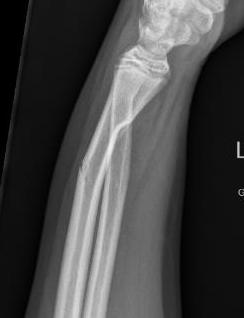

Greenstick fracture

- greeenstick fractures: unicortical fracture